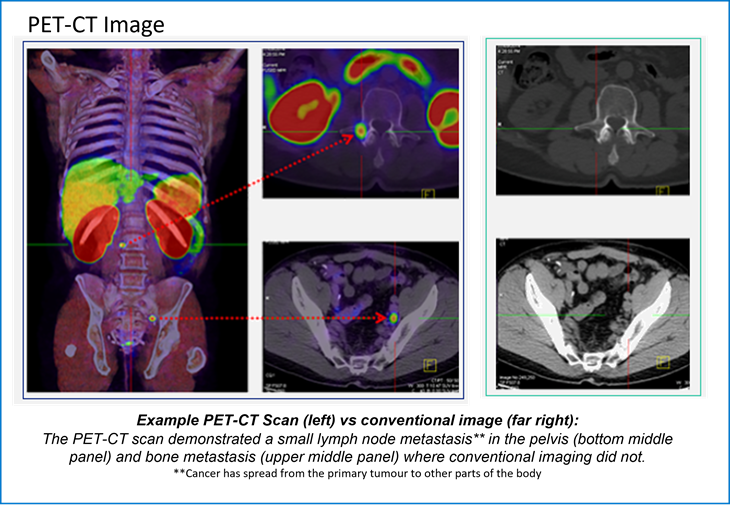

The PET-CT images ​